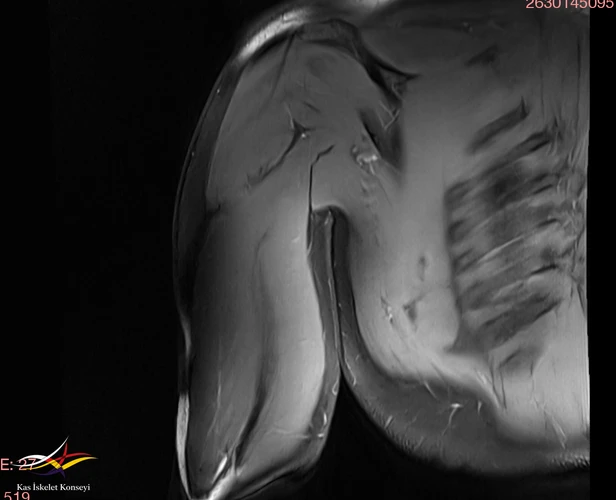

Brakiyal pleksus ve üst kol MRG normal rapor edilmiş.

Resim 2. Üst kol MRG: Normal.

Resim 3. Triceps görünümü.

Sevikal ve kol MRG normal olarak değerlendirildi. Brakial pleksus MRG optimal bulunmadı.